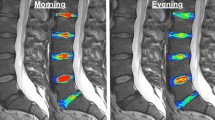

Signal intensity of the nucleus pulposus of the discs L2/L3–L4/L5 was visually assessed by two readers using the adjacent cerebrospinal fluid as an intensity reference. The weight (at age 25 and 40–45 y) and height of the subjects, history of car driving, smoking, and back injuries were assessed by questionnaire.